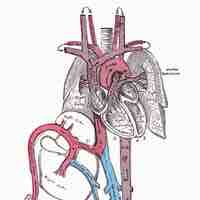

As a person ages, the walls of the heart thicken, the heart becomes heavier, valves stiffen and leak, and the aorta becomes larger.

Vasculogenesis is the development of new blood vessels.

New blood vessels are formed from endothelial stem cells, which give rise to the endothelial cells which line the vessels.

The fetal circulation includes the blood vessels within the placenta and the umbilical cord that carry fetal blood.